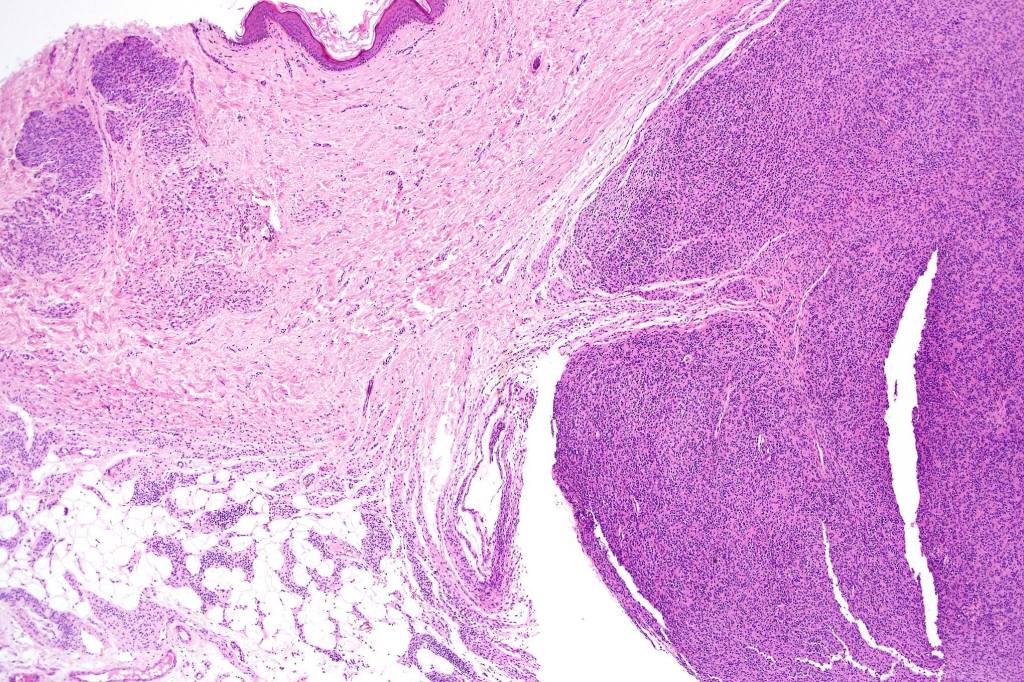

•The nodule generally merges with the adjacent nevus but sometimes it can be sharply circumscribed

•It is hypercellular and most often composed of epithelioid cells showing little pleomorphism & only occasional mitoses

•Absence of necrosis, hemorrhage or Pagetoid spread in the overlying epidermis

•Spindle cell, small blue cell, blue nevus-like features, Spitzoid & proliferative nodules with mesenchymal differentiation (myofibroblastic, chondroid & osteoid) can be seen